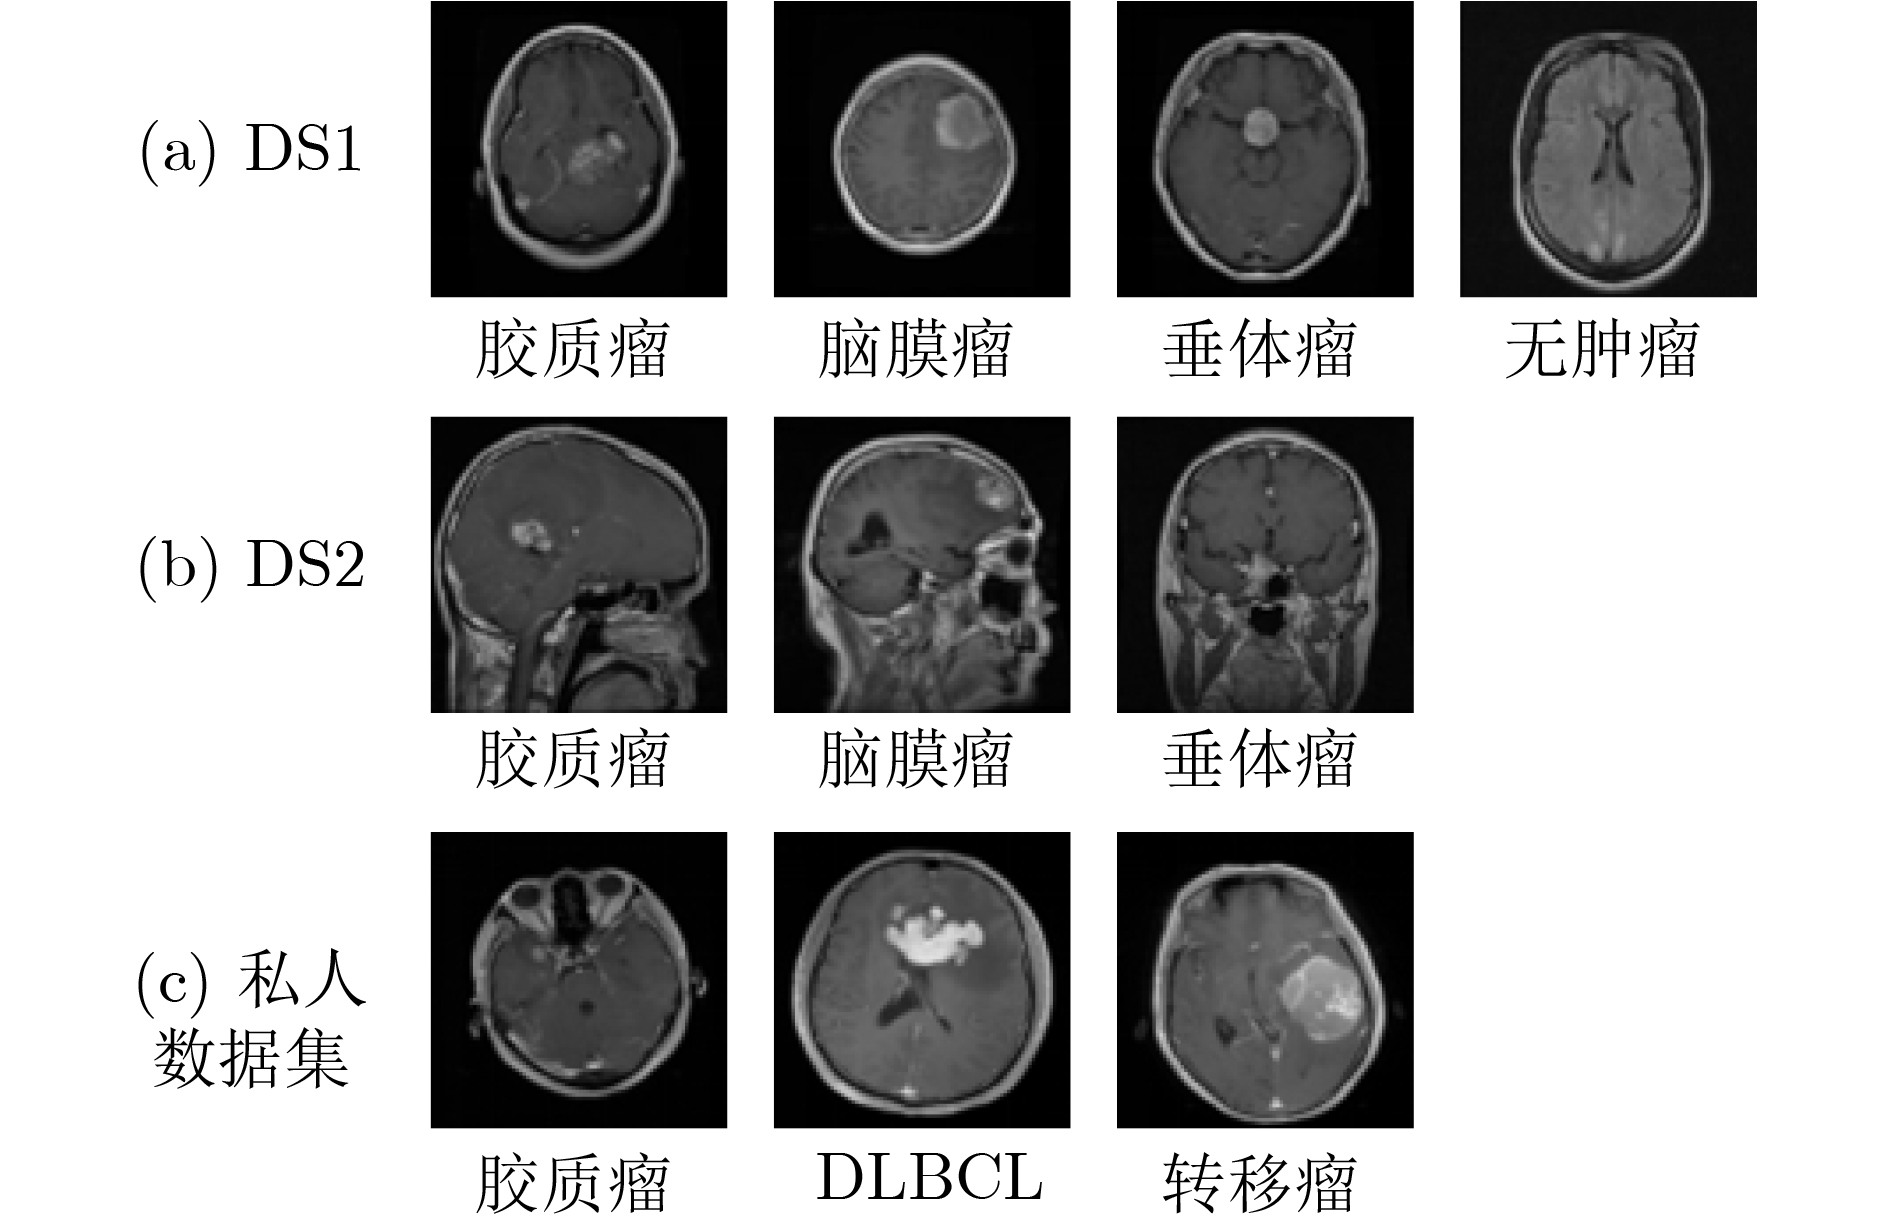

因果推理引导的KAN注意力脑肿瘤分类框架

樊亚文, 王翔, 岳震, 俞晓帆

2026, 48(3): 1056-1066. doi: 10.11999/JEIT250865

摘要:

脑肿瘤分类是医学影像分析中的关键任务,但现有深度学习方法在应对扫描参数差异、解剖位置偏移等因素时仍面临特征混淆问题,且难以建模肿瘤异质性引发的复杂非线性关系。针对这一挑战,该文提出一种因果推理引导的KAN注意力分类框架。首先,基于CLIP模型进行无监督特征提取,捕捉MRI数据中的高层语义特征;其次,基于K-means聚类设计混淆均衡度指标,筛选混淆因子图像,并设计因果干预机制,显式引入混淆样本,同时提出因果增强的损失函数以优化模型的判别能力;最后,在预训练ResNet主干网中引入KAN注意力模块,强化模型对肿瘤局部坏死区与强化边缘的非线性关联建模能力。实验表明,所提出的方法在脑肿瘤分类任务中优于传统CNN与Transformer模型,验证了其在判别能力和鲁棒性方面的优势。该研究为医学影像的因果推理与高阶非线性建模提供了新的技术路径。